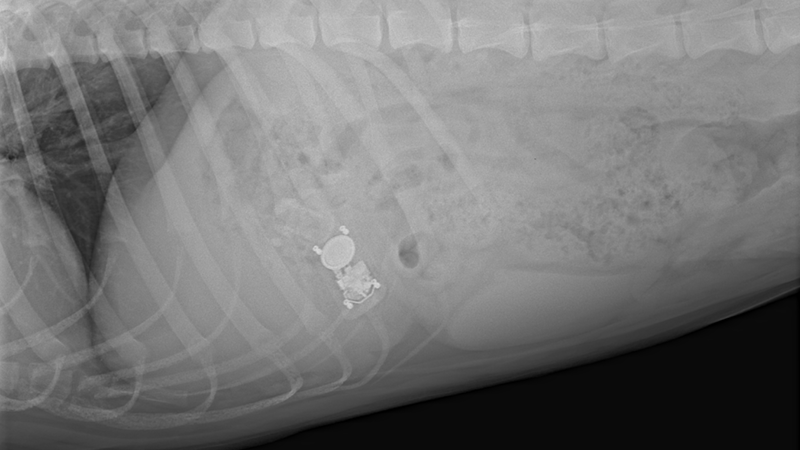

This procedure provides high-quality, real-time imaging that helps specialists identify inflammation, masses, ulcers, strictures, or foreign objects – which can be life-threatening. Learn more about gastrointestinal foreign bodies in our blog post. It also enables veterinarians to collect biopsy samples using minimally invasive instruments, which are essential for accurate diagnosis.

- In some cases, polyps or small foreign bodies can be removed.

- Foreign body ingestion

- Large or sharp foreign bodies that cannot be safely removed via endoscopy